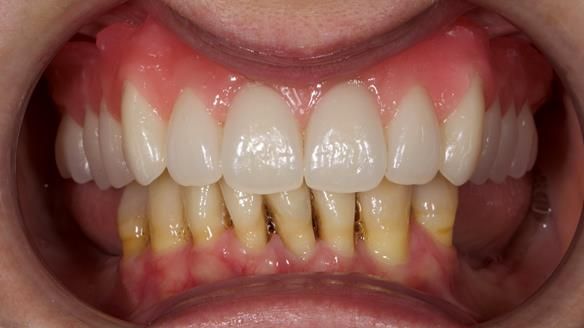

She had previously suffered from generalised periodontitis – stage IV, grade C, currently stable, with reduced attachment across the upper arch.

By the time she came to me, her periodontal condition was stable — but the aesthetics in the upper jaw were very poor.

We provided her with an immediate upper denture (Mk 1), followed by a definitive metal-based upper denture (Mk 2). A lower removable partial denture was discussed, to be made only if needed once the upper treatment was complete. However, at review, this wasn’t necessary — Adnana had excellent neuromuscular control and function, even with a shortened dental arch (SDA).

Rowan, Sam Hesketh and Chris Hesketh provided the stunning technical work. I am very lucky to have them.

- Immediate denture (Mk 1) fitted the same day the teeth came out

- Definitive denture (Mk 2), metal-based and custom-designed for her face

- A restored smile, restored lip support, and a patient who owned the journey